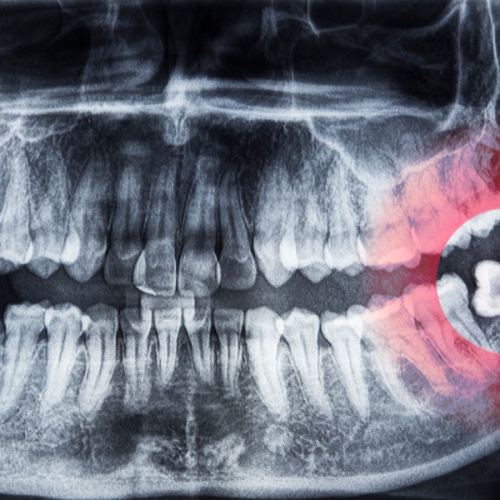

At Dantaa Dental Clinic, we will start with a thorough evaluation to find out where your wisdom teeth are located through either X-rays or 3D imaging. This helps patients understand the condition clearly, especially those visiting us for wisdom teeth removal in Chandigarh.

- Bony Impaction: The most complex category, where the tooth is completely or partially within the jawbone as shown by dental experts.